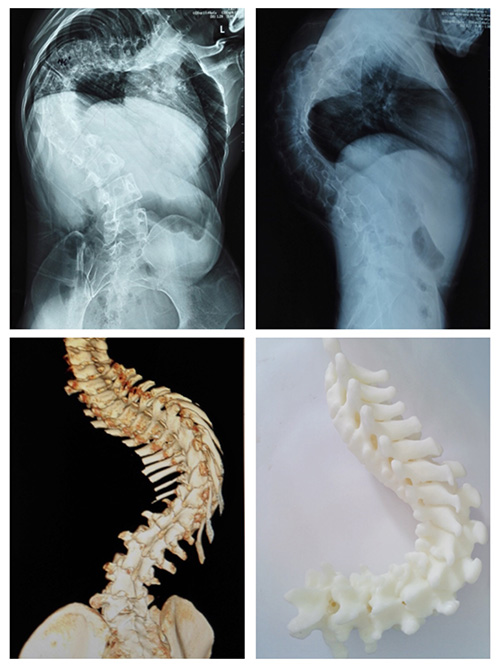

入院后,医生对她进行术前检查,发现陶某侧弯较重,侧弯Cob角达140°,后凸Cob角达105°。

骨科医生经过对李某进行脊柱X线片,三维CT及MRI等项检查,发现侧弯Cob角达135°,后凸Cob角达80°,并发现患者胸椎有半椎体畸形。

术后患者外观均有明显改善。

其中陶某侧弯Cob减小50°,后凸Cob角减小30°。

李某侧弯Cob减小50°,后凸Cob角减小30°。